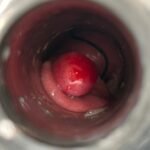

LASER LIAS FOR ANAL FISSURES AND BANDING OF HEMORRHOIDS